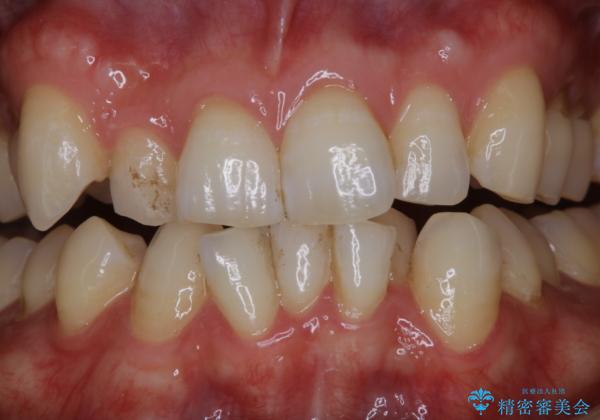

- 前歯の汚れが気になるため、綺麗にしたいとのことで来院されました。PMTC30分コースを行いました。

毎日丁寧に歯磨きをしていても、日常生活での飲食物などにより着色してしまうことはあります。PMTCでは、歯の表面の凸凹にミネラルを補給して、ツルツルの表面に仕上げます。定期的にPMTCを行うことにより、歯質の強化になり着色がつきにくい状態になります。